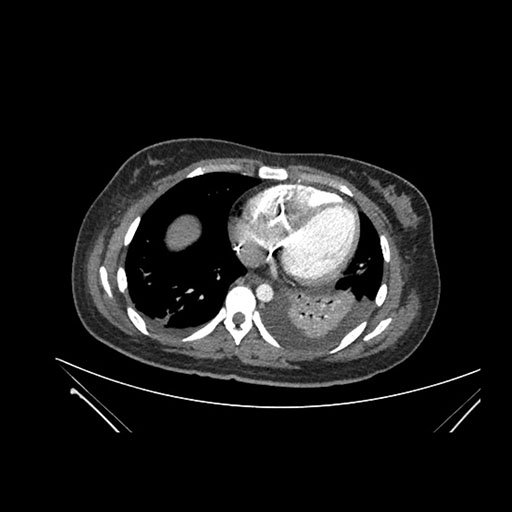

Axial Arterial

Axial Venous